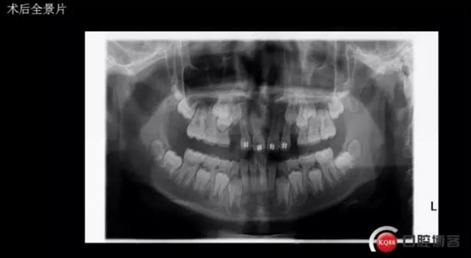

術(shù)后思考:患兒如今已經(jīng)十一歲多, 雖然已經(jīng)給尖牙騰出了位置,然而全景片顯示兩顆尖牙位置依然很深,是主動出擊還是靜觀其變呢?歡迎大家共同探討!